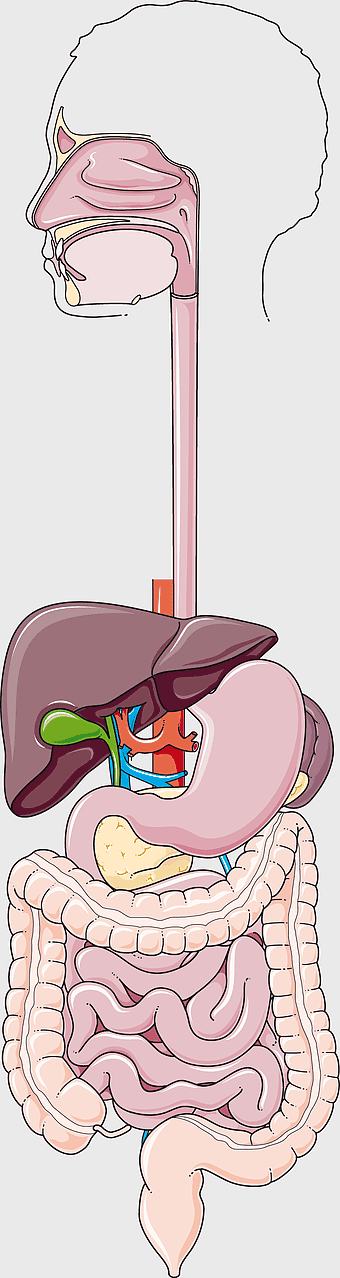

human gastrointestinal tract anatomy, human digestive system illustration, gastrointestinal disease symptoms, human body organ diagram, internal organ visualization, medical anatomy study, digestive health awareness -

Crohn's disease illustration, gastrointestinal tract diagram, large intestine anatomy, digestive system cartoon, medical illustration, human anatomy study, chronic inflammatory bowel condition -

human digestive system, gastrointestinal tract anatomy, liver function, stomach and intestines, digestive health, internal organs diagram, human body systems -

Gastrointestinal tract anatomy, Stomach health, Crohn's disease symptoms, Digestive system, Intestinal inflammation, Human anatomy illustration, Medical diagram -

digestive system diagram, gastrointestinal tract chart, human anatomy illustration, small intestine function, digestive process visualization, internal organ layout, metabolic system overview -

human digestive system illustration, gastrointestinal tract diagram, human body organ system, labeled digestive system, digestive anatomy chart, human internal organs, alimentary canal visualization -

Gastrointestinal tract diagram, Small intestine anatomy, Large intestine function, Apparato digerente illustration, Digestive system structure, Intestinal health, Human anatomy organs -

Gastrointestinal tract illustration, leaky gut syndrome symptoms, small intestine diagram, large intestine function, digestive system health, human anatomy chart, internal organ visualization -